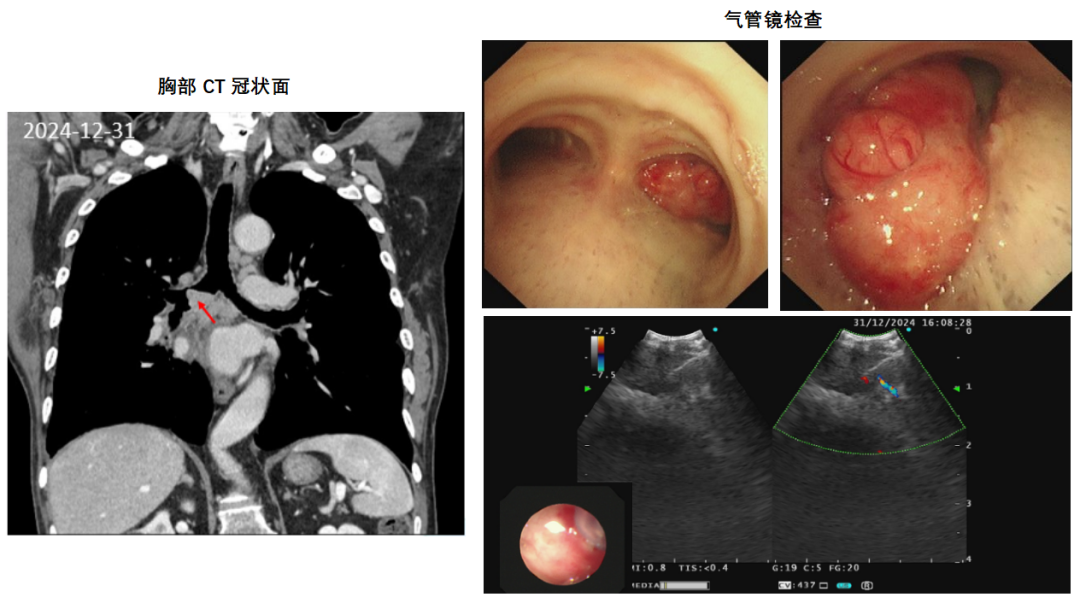

2024-12-30胸部CT见右主支气管结节(1.5cm×1.2cm),纵隔淋巴结肿大(图4)。入院查体:体温36.6,血压106/79mmHg,心率73次/分,呼吸频率20次/分,血氧饱和度98%。皮肤巩膜无黄染,无皮疹包块,全身浅表淋巴结未触及。听诊右肺呼吸音低,未闻及明显干湿啰音,心界无扩大,心律齐,各瓣膜区未闻及杂音。腹软,无压痛,肝脾肋下未触及,双下肢无浮肿,神经系统无异常,无皮下气肿,无杵状指,颈静脉无怒张。实验室检查示:

支气管镜见右主支气管开口新生物堵塞伴管腔狭窄(狭窄约80%),表面充血易出血,初步考虑中心气道狭窄分级:右主支气管,狭窄程度:Ⅳ级(76-90%)狭窄长度:~2cm,结合患者肿瘤病史以及移植后长期抗排异治疗,考虑新生物为肺癌复发或感染性病变可能,经验性予莫西沙星针0.4 qd抗感染,并行支气管镜介入治疗清除病变组织以及超声支气管镜引导下经支气管针吸活检(EBUS-TBNA)术。

图4 2024-12-30胸部CT示右主支气管结节(红色箭头),纵隔淋巴结肿大;气管镜示右主支气管开口新生物堵塞伴管腔狭窄;超声支气管镜下7组纵隔淋巴结TBNA术